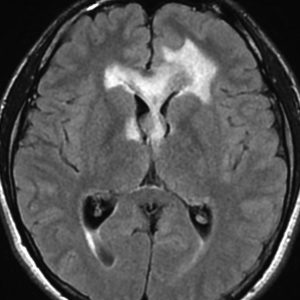

ガドリニウム増強では,前頭葉腫瘍というより,側脳室壁にベトベトくっついているような腫瘍です。germinoma特有のsubependymal infiltration像を示します。

生検後2ヶ月,セカンドオピニオンのために受診された時の画像です。腫瘍が縮小傾向にあります。入院中に行われた何度かのCT被曝の影響で,germinomaの退縮が生じたのだと判断しました。